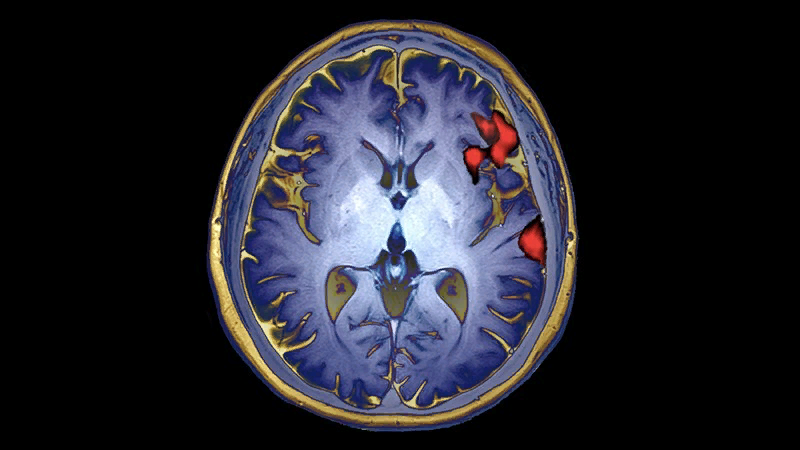

Нейробиолог Скотт Марек провёл масштабное исследование, посвящённое развитию мозга детей. Для этого он вместе с коллегами проанализировал данные о 2 тысячах детей. Постепенно число этих данных увеличилось. В итоге оказалось, что связи между функциями мозга, поведением человека и результатами сканирования головного мозга практически нет. Точнее, этой информации недостаточно, чтобы точно сделать вывод о поведении ребёнка.

Скотт Марек и Нико Досенбах (нейробиолог из WashU) с другими учёными также обнаружили при сравнении данных о результатах МРТ-сканирования и о поведении участников исследований, что повторения каких-то ассоциаций или связей между ними встречались довольно редко и не во всех научных работах. К примеру, если брать исследование, где участвовали 2 тысячи человек, то эти ассоциации повторялись лишь в 25 % случаев, а если говорить об эксперименте с участием 500 человек или меньше, то надёжные ассоциации встречались только в 5 % случаев.